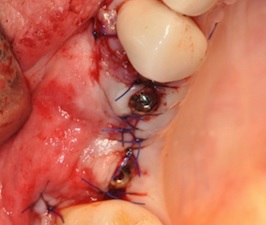

Paslaugos: Chirurgija, Dantų balinimas, Vaikų dantų gydymas, Dantų šaknų kanalų gydymas, Estetinis plombavimas, Dantų šaknų kanalų pergydymas